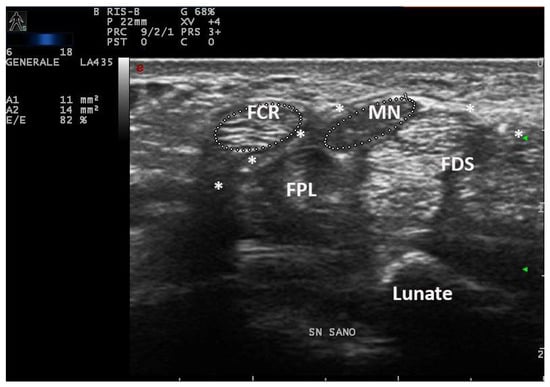

On the same day of EDS, every patient underwent a high-resolution US examination (4–15 MHz and 8–24 MHz linear probes, MyLab X8 eXP Esaote and 6–18 MHz linear probe, MyLab Twice, Esaote, Genoa, Italy) of the carpal tunnel in the Rheumatology Unit of the same hospital. The examination was performed by a single rheumatologist with 20 years of experience in musculoskeletal US and blinded to clinical and electrophysiologic CTS severity. Patients were seated in a chair with arms extended, hands resting in a horizontal supine position and fingers relaxed. The median nerve cross-sectional area (CSA) was measured at the tunnel inlet (just before the proximal margin of the flexor retinaculum) by tracing the inner border of the thin hyperechoic rim of the nerve (perineurium) with the automatic ellipsoid technique (or manual tracing technique if the nerve had an irregular shape). Moreover, the CSA of flexor carpi radialis (FCR-CSA) was measured over (or just proximal to) the scaphoid tubercle, where the tendon runs parallel to the skin (possibly in the same scan of MN-CSA, with the automatic ellipsoid technique). The ratio between the two CSAs was calculated and recorded as the nerve tendon ratio (NTR) (expressed as a percentage) (Figure 2). The probe was applied without additional pressure, and the mean value of three measurements, along with clinical and anthropometric characteristics (weight, height, wrist circumference), was recorded.

Figure 2. Transverse scan over left and right carpal tunnels in male patient (172 cm × 82 kg, 18.5 cm of wrist circumference) affected with extremely severe CTS (Padua Scale 5 bilaterally). Linear 4–15 MHz probe. Both MN-CSA show frankly pathologic values (Area 1, left: 17 mm2, Area 3, right: 14 mm2). NTR is calculated as the ratio between MN-CSA and FCR-CSA (expressed as a percentage), and shows bilaterally pathologic values (left 143%, right 119%) indicative for severe CTS. MN = median nerve, FCR = flexor carpi radialis.